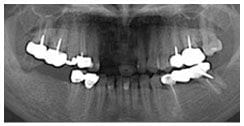

X 光片

術前X光片

術後X光片